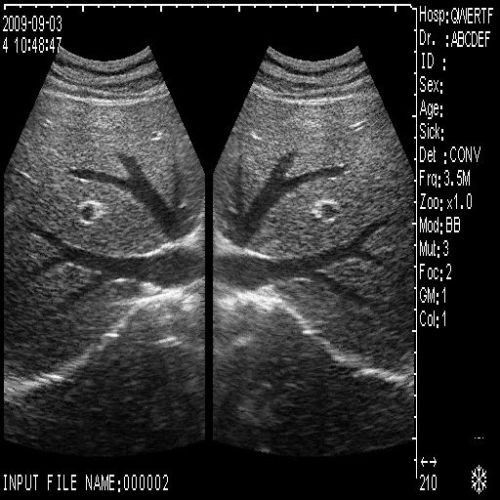

image: +3D High clear

Probe Function: 3.5MHZ convex, abdominal organs

The Diagnostic Ultrasound Scanner provides a comprehensive solution for medical practitioners. It includes both convex and transvaginal probes, allowing for versatile imaging options. With the ability to create detailed images of various organs, this machine significantly improves diagnostic accuracy. Moreover, doctors can perform thorough examinations quickly and easily, so they can identify medical conditions early. As a result, patients receive timely care that can lead to better health outcomes.

Exceptional 3D Imaging Technology

This ultrasound scanner features cutting-edge 3D imaging technology, which enhances visualization during diagnostic procedures. The high-resolution images produced help healthcare professionals to analyze anatomical structures in greater detail. Additionally, the scanner’s user-friendly interface simplifies the imaging process, ensuring that practitioners can focus on patient care rather than complex setups. Therefore, this device aids in both efficiency and effectiveness in clinical settings.